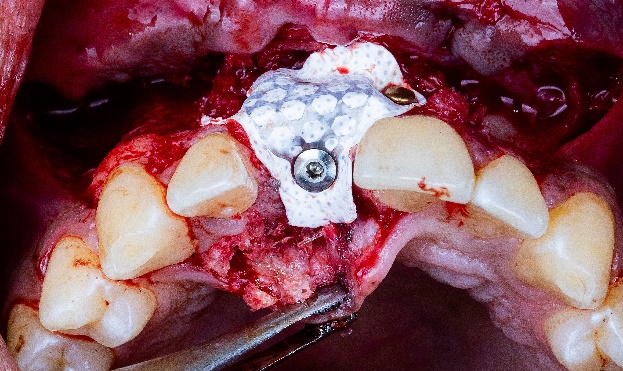

Ход лечения: Установка имплантатов по шаблону и минимально инвазивная операция по наращиванию кости

Хирургический шаблон был напечатан из прозрачного фотополимера с помощью 3D-принтера AccuFab-D1s от Shining 3D. Шаблон закрепили в полости рта, и он точно указал зону наращивания кости. Отверстие под имплантат было поэтапно просверлено через шаблон. Затем доктор вкрутил сам имплантат, который показал превосходную первичную стабилизацию. (Рис. 9, Рис. 10)

Рис. 9, Рис. 10: Установка имплантата с помощью хирургического шаблона.

После установки имплантата доктор ввел костный материал и накрыл его нерассасывающейся мембраной из политетрафтороэтилена (ПТФЭ), усиленной титановым каркасом. Такая мембрана предотвращает врастание в нее мягких тканей. Края мембраны были закреплены титановыми пинами (рис. 11, 12).

Рис. 11, Рис. 12: Операция по направленному наращиванию костной ткани.